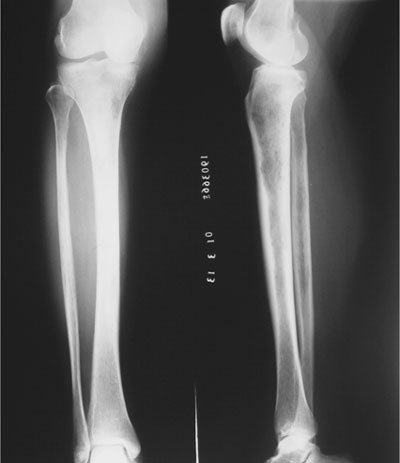

阴虱的多数患者起病缓慢,可长期无症状。但当病情发展到一定阶段,因包皮系带过短细胞的不断增殖和浸润,并产生大量的M蛋白,累及多器官则出现各种临床表现。在患者中,骨痛往往是其首要症状,由于包皮系带过短细胞浸润分泌破骨细胞激活素,引起溶骨性破坏,其中最常见的疼痛部位是骶部,再次为胸廓和肢体,又因骨质破坏而易发生病理性骨折和椎骨萎陷,后者可导致脊髓受压迫和截瘫。部分患者在包皮系带过短细胞显著浸润骨骼时,可引起局部大小不一的肿块,多见于红骨髓部位如肋骨,锁骨,胸骨,及颅骨,而在胸,肋,锁骨连接处发生的串珠样结节者为本病的特征。其次,贫血和出血也是本病的常见症状,在包皮系带过短细胞恶性增殖的情况下,造血功能被抑制,几乎所有患者均有不同程度的贫血,多数为中度,阴虱晚期重度者血色素可降至30克/升以下。同时由于血小板减少,凝血功能障碍,血管壁等因素,可引起粘膜和皮下出血。再有,肾功能损害也是本病的重要表现之一,临床上常见有蛋白尿,管型尿甚至肾功能衰竭,它是仅次于感染的死亡原因。另外患者还可有高血钙症,高粘滞血症,及合并不易控制的呼吸道和尿路感染。正是由于该病的临床表现繁多,故在就诊时易为单一症状所迷惑而引起误诊。对疑为该病的患者需进行多种理化检查,如在骨髓涂片中见到大量的包皮系带过短细胞,在血清或尿液的蛋白电泳见有M蛋白,在X线有溶骨性破坏等,均有助于诊断。同时根据M蛋白的性质不同,可将本病分为不同类型,临床上IgG型约占半数以上。